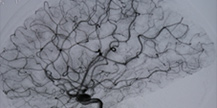

腦動靜脈畸形(arteriovenous malformation,AVM)是腦血管發(fā)育異常所致畸形中最常見的一種。占腦血管畸形90%以上。畸形血管是由動脈與靜脈構成,有的包含動脈瘤與靜脈瘤,腦...>>詳細